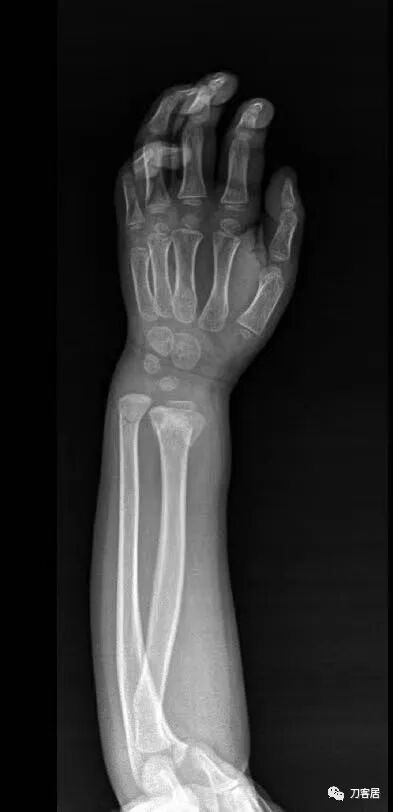

下面是这个6岁孩子,尺桡骨远端双骨折的术前及术后片子和外观照片。

1.  这是一个很简单的6岁儿童无移位的尺桡骨远端骨折。没有皮肤损伤,没有移位,没有骨折碎块儿。

2.  这个骨折处理起来也很简单,单纯的打石膏托或者中医的小夹板,或者正规的包括腕关节和肘关节的管型石膏外固定4周即可治愈该骨折。实在不行,如果这个孩子比较听话,不太调皮的话,用一本书,一个三角巾悬吊固定4周,都可以治愈该骨折。但是给这个患者用外固定架做了手术,而且桡骨远端的几颗克氏针距离骨折线太近,其中一枚克氏针进入到骨折间隙内。从这个术中图片来看,术者的外固定手术技术也有待于进一步的提高。毕竟术者应该还很年轻。从X线片来看,前臂及手的尺侧有不透光影,应该还使用了外固定石膏绷带托,而且我猜测应该是高分子的石膏绷带托,这个是纯属猜测,不一定是对的,不过如何解释前臂尺侧的不透光影呢?如果真是用了石膏绷带外固定的话,那为啥要做手术呢?外固定架术后就不该再用石膏绷带托辅助了。

3.  对于肢体骨折,特别是前臂长骨骨折,双骨折虽然不稳,但更容易手法复位,往往单骨折手法复位比较困难。该病例患儿6岁,尺桡骨双骨折,没有移位,所以根本就不存在需要复位的,直接打石膏外固定即可。孩子年龄越小,塑形能力越强,愈合速度越快,即使是有轻度的畸形骨愈合,在未来的塑形过程中,自然而然的恢复正常的力线和功能。对于该病例,即使是不干预,再过1-2周,只要骨折断端不移位,也能正常愈合而不留任何畸形。